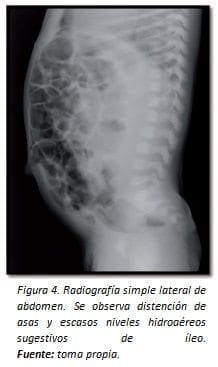

Se solicitó la práctica de hemograma y PCR, los cuales no representaron riesgo para infección, y radiografía de abdomen que mostró distención de asas y escasos niveles hidroaéreos sugestivos de íleo (Figura 4).

Una radiografía de control a las 6 horas evidenció la presencia de aire extraluminal (Figuras 5 y 6) por lo cual se sospechó sobre la perforación del asa intestinal. De acuerdo con lo anterior, se inició un manejo antibiótico empírico y se remitió al paciente a laparatomía exploratoria.